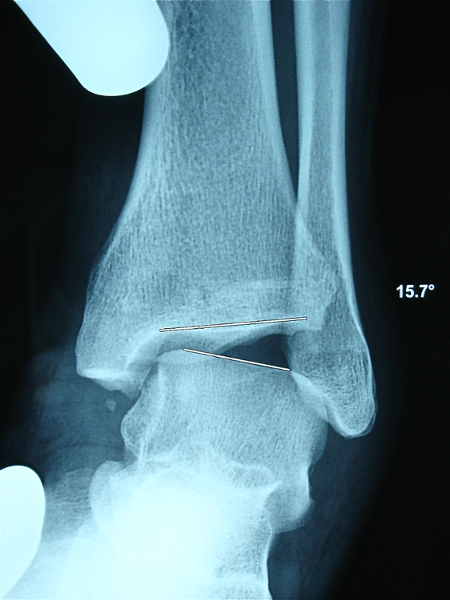

DES CLICHES DYNAMIQUES:

il s'agit de reproduire le mouvement anormal de baillement de l'articulation en le comparant au côté opposé.

Ils peuvent se faire manuellement ou de manière optimale avec le dispositif TELOS.

Ce dispositif comprend un étau et un poussoir qui permet de produire une poussée toujours identique.

cliché en varus avec TELOS 14° |

Une ouverture articulaire (ou diasthasis) formant un angle supérieur à 10° avec une différence de plus de 2° avec le côté opposé est considéré comme pathologique.